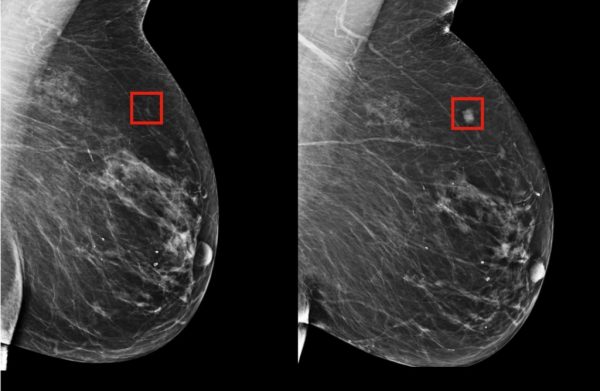

Indicó que es importante buscar nuevas herramientas que ayuden al análisis y control de esta enfermedad, pero sobre todo en los tiempos entre la detección y el acceso al tratamiento del Cáncer de Mama en las mujeres vulnerables o de escasos recursos. “Desde el Partido del Trabajo de la Ciudad de México llamamos a todas las mujeres a que se practiquen la autoexploración de forma regular, con el fin de detectar cualquier cambio en sus mamas, así como la periodicidad en los estudios de mastografía” exhortó.